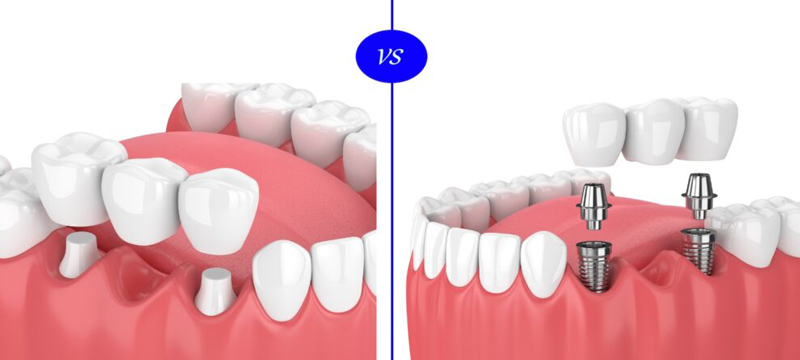

بریج دندان (Dental Bridge) نوعی پروتز ثابت است که با تکیه بر دندانهای مجاور، جای خالی دندان از دسترفته را پر میکند. در این روش، معمولاً دندانهای کناری تراشیده میشوند تا بتوانند نقش پایه بریج را ایفا کنند. در مقابل، ایمپلنت دندان (Dental Implant) پایهای فلزی و پیچشکل است که مستقیماً درون استخوان فک جای میگیرد و بهمرور با استخوان جوش میخورد. سپس یک تاج دندانی روی آن قرار میگیرد که کاملاً شبیه دندان طبیعی عمل میکند و نیازی به آسیب به دندانهای اطراف ندارد.

برای مقایسه پل دندان و ایمپلنت، در ابتدا باید به تعریف هر کدام از این موارد بپردازیم. در روش پل دندان یا بریج، دندان های کناری به عنوان پایه دندان از دست رفته، مورد استفاده قرار می گیرند. در واقع دندانپزشک برای پر کردن جای خالی دندان از دست رفته، از بریج استفاده می کند. بریج نوعی دندان مصنوعی ثابت است که از یک یا چند دندان و دو روکش در دو سمت آنها تشکیل شده است.

این روکش ها با قرارگیری بر روی دندان های اطراف دندان از دست رفته، می توانند ثبات دندان مصنوعی را حفظ کنند. برای ساخت پل دندان، از مواد مختلفی مانند سرامیک، طلا، چینی و … استفاده می شود که نوع سرامیک آن به دلیل شباهت ظاهری زیاد به دندان طبیعی، طرفداران بیشتری دارد. بریج ها انواع مختلفی دارند که شامل سنتی یا ساده، کانتیلور یا معلق، بریج مریلند و همراه با ایمپلنت می شوند. حال ایمپلنت نیز به پل دندانی شباهت زیادی دارد؛ با این تفاوت که در بریج ها پایه دندان، همان ریشه اصلی دندان است.

اما در ایمپلنت، با ایجاد یک ریشه مصنوعی، یک پایه برای روکش دندان تشکیل می دهند. این روزها ایمپلنت، یکی از بهترین راهکارها برای جبران دندان از دست رفته است. این روش، تاثیر به سزایی در ظاهر، تکلم و بهبود جویدن غذا دارد. کاشت ایمپلنت دندان، انواع مختلفی دارد که شامل ایمپلنت های تک دندان، دندان فوری، بر اساس پونتیک، جراحی های لیفت سینوس و جراحی بازسازی استخوان فک می شود. هر کدام از این دو روش، دارای مزایا و معایبی هستند.